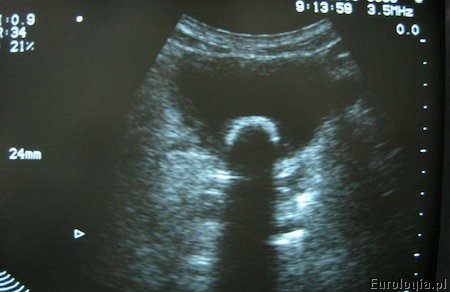

Fot. Kamień w pęcherzu moczowym - obraz USG.

Z powodu nawracającego zapalenia pęcherza moczowego trafiłem do urologa. Po wykonaniu USG jamy brzusznej urolog stwierdził, że mam kamień w pęcherzu moczowym. Średnica kamienia to 2 cm. Mam 35 lat i zastanawiam się jak można usunąć taki kamień z pęcherza. Czy operacja laparoskopowa usunięcia kamienia jest możliwa?